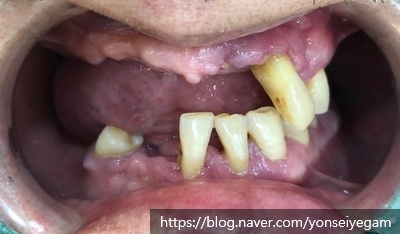

아래쪽 빠진 치아의 부분과 위 앞니는 내비게이션 임플란트 시행하여 머리까지 올라갔고

위쪽 어금니 치아는 틀니진행중 찍은 사진입니다.(사진의 어금니 위치아는 임시틀니)